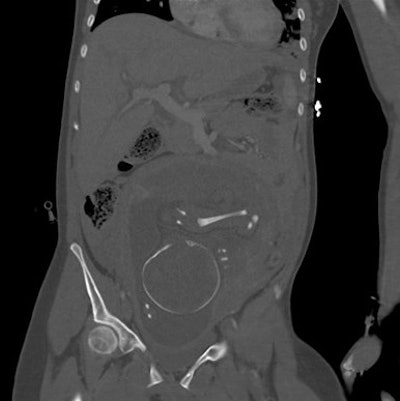

- 8 abdominopelvic CT exams

The number of CT exams of pregnant patients increased from three to four per year in 2008 to 2011 to 11 per year in 2012, a result that corresponding author Dr. Federica Zanca, also from University Hospitals Leuven, called "surprising" in an email to AuntMinnieEurope.com. In addition, three pregnancies were found by accident on abdominopelvic CT, which Zanca said was also surprising.

Abdominopelvic CT | 28.7 (range: 6.7-60.5) |

The radiation dose for all but the abdominopelvic CT exams were considered negligible, according to the researchers.

The results are largely in line with current literature on clinical indications and typical radiation doses to the fetus during CT exams. In only two of the trauma exams, the estimated doses were much higher than those reported in the literature.